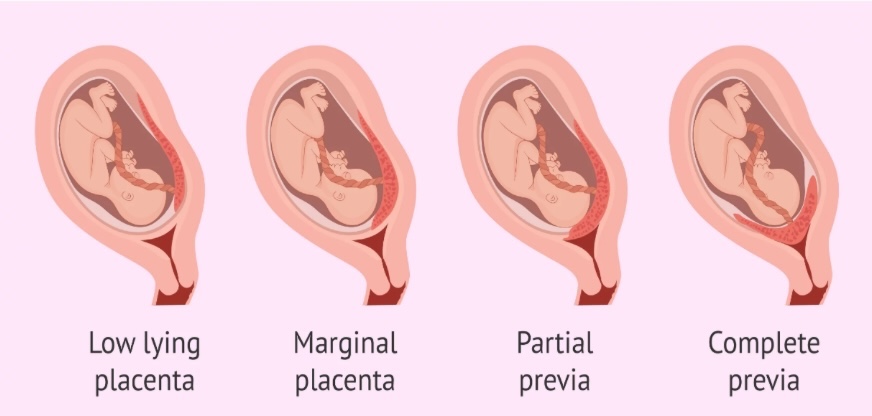

Rau tiền đạo (Placenta previa) là tình trạng nhau thai bám bất thường ở đoạn dưới tử cung, che một phần hoặc toàn bộ lỗ cổ tử cung. Khi tử cung lớn lên trong thai kỳ, vị trí bánh rau này có thể gây chảy máu âm đạo dữ dội, đặc biệt là trong 3 tháng cuối, gây nguy hiểm cho cả mẹ và bé.

Hình ảnh mô phỏng các vị trí rau bám bất thường: Rau bám thấp, rau tiền đạo, bám mép,….